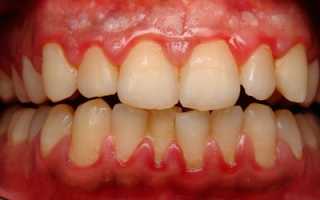

Признаки хронической формы:

Фото 2. Хроническая форма заболевания проявляется застойным переполнением кровью сосудов и отёчностью слизистой дёсен, кровоточивостью и деформацией десны.

- опухшее состояние десны;

- болевые ощущения во время приёма пищи;

- болезненность во время чистки зубов;

- переполнение крови в десне;

- отслаивание дёсенных сосочков от зубов.

Выявить хроническую форму гингивита сможет только врач.